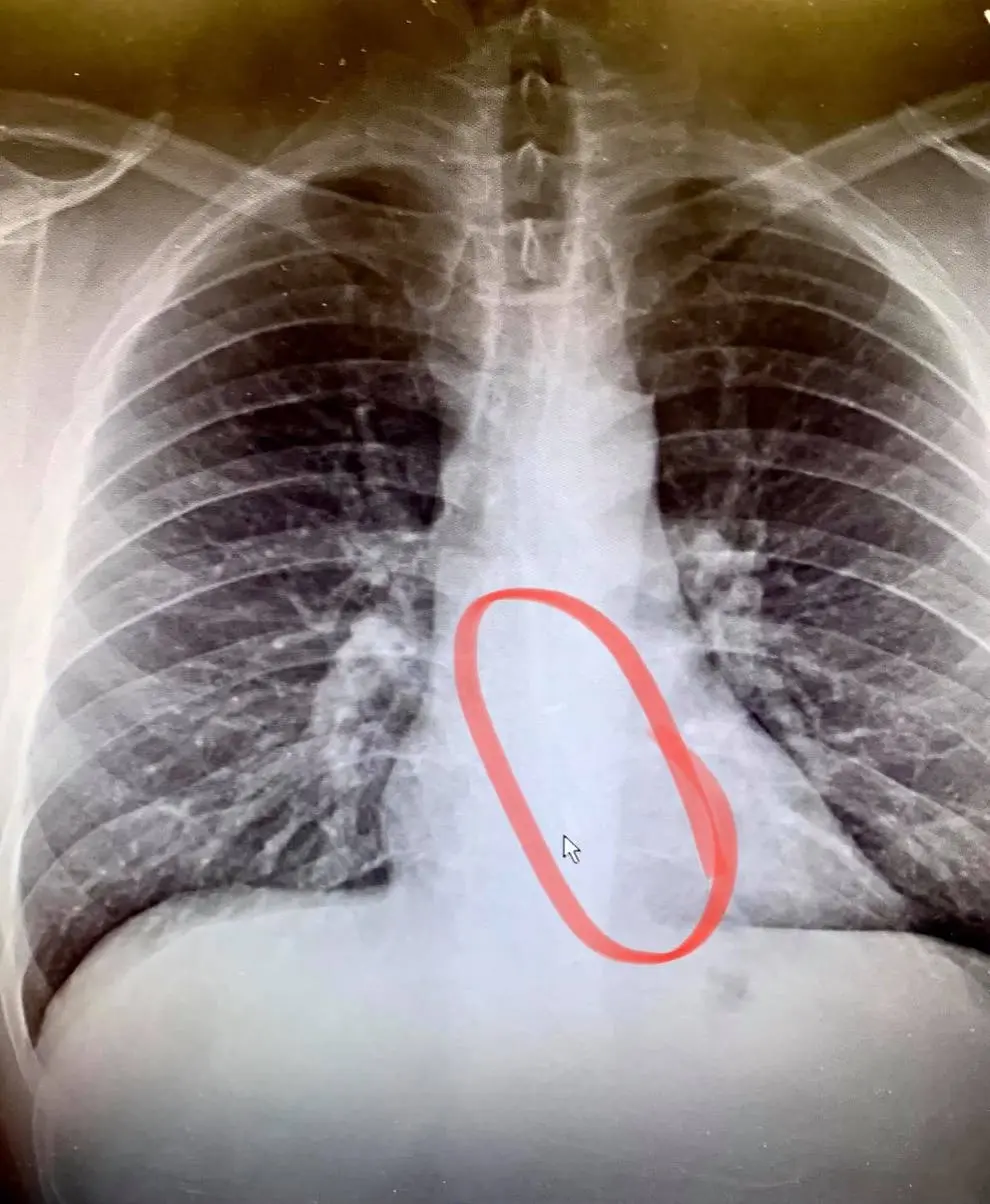

อย่างไรก็ดี นายโกว์เธียร์ได้ตัดสินใจไปหาพบแพทย์ เนื่องจากยังคงมีอาการเจ็บที่หน้าอก ซึ่งแพทย์ได้พาเขาไปเอ็กซ์เรย์ จึงพบว่าภายในลำคอของเขามีหูฟัง AirPods ขนาดความยาว 2 นิ้วอยู่ข้างใน โดยหูฟังดังกล่าวอยู่ในบริเวณหลอดอาหารของเขานานถึง 24 ชั่วโมง